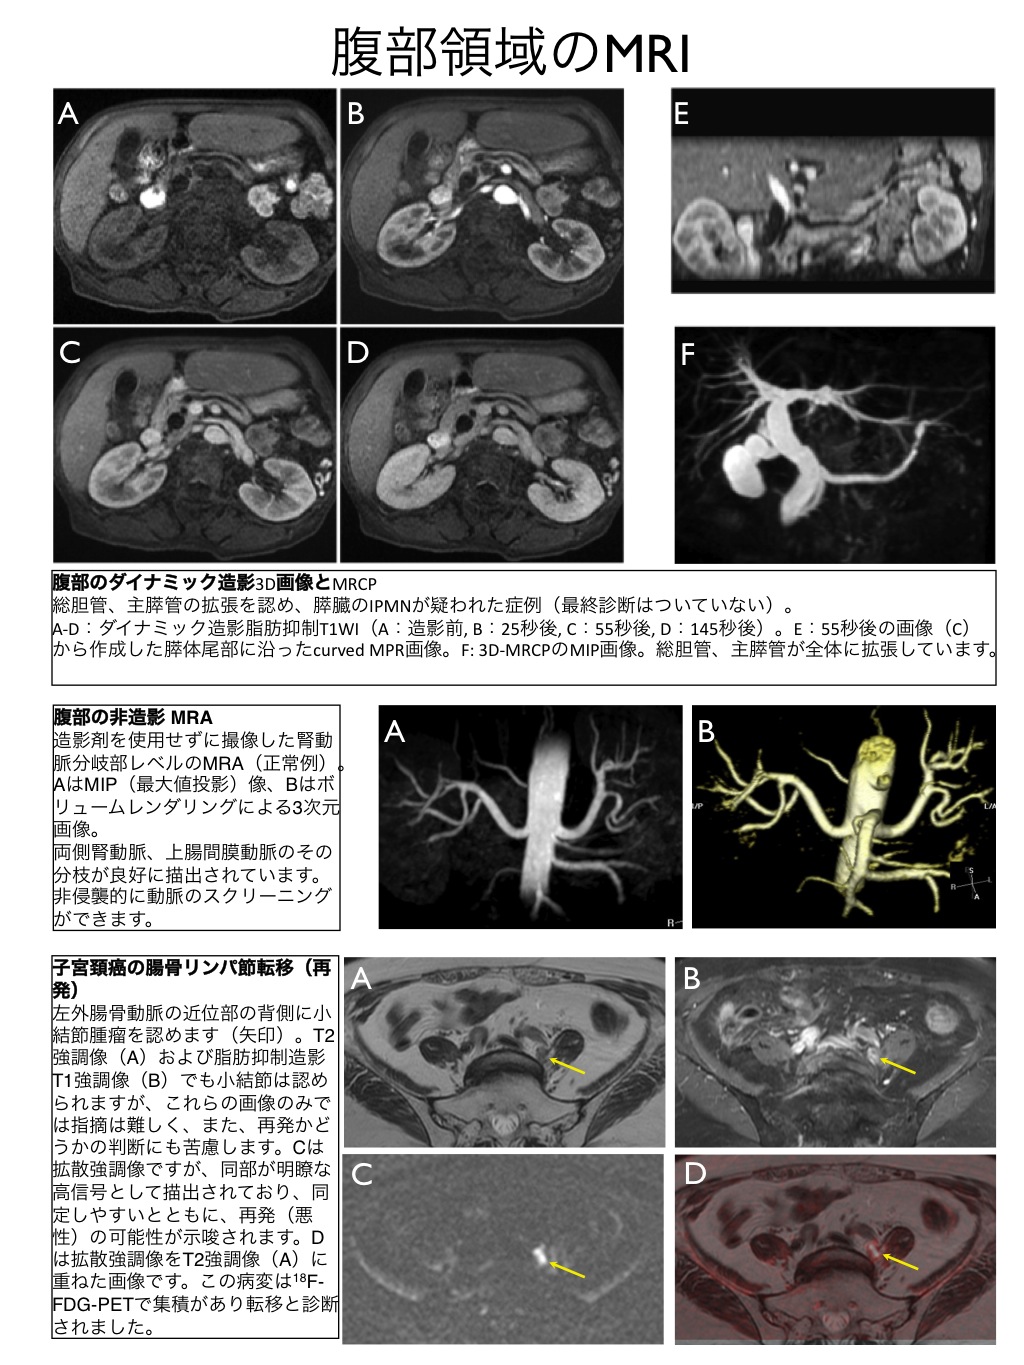

Seminar Report 第23回腹部放射線研究会 ランチョンセミナー 腹部 骨盤部の3t Mriの有用性 Magnetom シーメンス ジャパン株式会社 Innavi Suite

MixiMRI勉強会 脂肪抑制いろいろ 最近やっと勉強する気になったのですが、疑問が次から次へと出てきます。ここでは脂肪抑制についてお聞きしたいと思います。 脂肪抑制にもいろいろありますよね。 T2、PD、T1など。また、SE系、GRE系の違いもありま. ・骨盤部ではmriを,腹部ではctを第一選択にする. ・t1強調画像ではt1が長いほど磁化の回復が遅れるため信号が低く(黒く),t2強調画像ではt2 が長いほど磁化の減衰が遅れるため信号が高く(白く)描出される.t1とt2の組み合わせで組 t1強調画像はctの画像と似ており、脳の解剖学的な構造が見やすいという特徴があります。. 造影剤投与によりT1緩和時間が大きく短縮されますので基本的に脂肪抑制T1強調画像をベースに撮影が行われます。 ③実際の症例を提示します。 1) Stage I 腎細胞癌のdynamic MRI画像です。 左腎臓上極に1cm大の遷延性濃染する腫瘍を認めます。.

MRI(magnetic resonance imaging)検査では撮像 時間が長く,上腹部の検査では,呼吸による動きによ ってモーションアーチファクト(mortion artifact:運 動アーチファクト)が発生し,読影診断に影響を与え てしまうおそれがある.呼吸のような周期的な動きに. 3T MRI が臨床に導入されてから、基本的な撮像技術の重要性がますます高まっている。本講演では、3T MRIにおける躯幹部領域のトピックスである、脂肪抑制、Volume化の流れ、非造影MRAの3点について、GE社MRIの最新アプリケーションと臨床的有用性を中心に紹介する。. く,造影剤が分布した周囲組織のプロトンの緩和を促進(主としてt1短縮効 果)させることにより,t1強調画像で造影効果を発揮する(信号が増強される)。 しかしながら,造影剤濃度が高くなると,t2,t2*短縮効果により信号は逆に 減衰する(図1)2)。.

腹部領域におけるmri最新技術 非侵襲的アプローチを中心に 技術解説 Geヘルスケア ジャパン株式会社 Innavi Suite